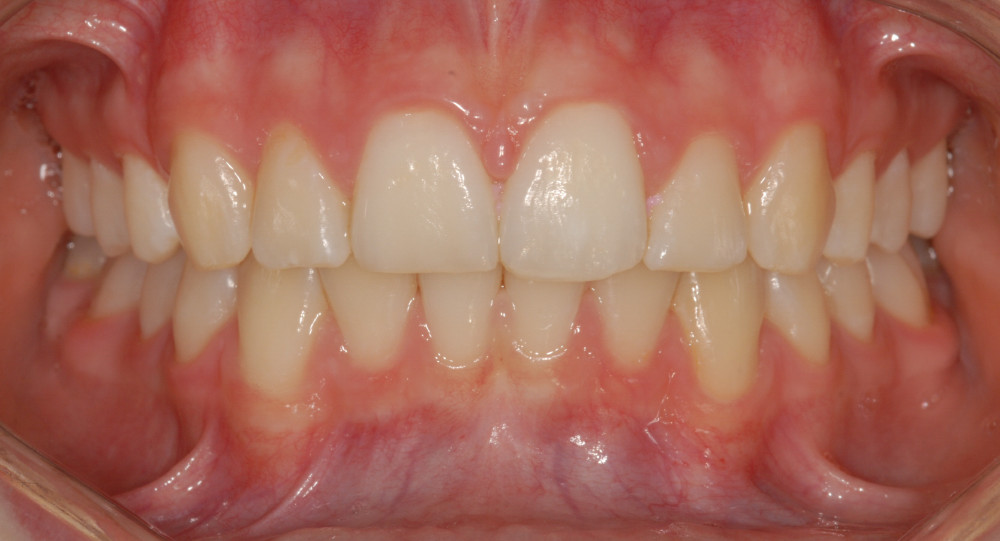

- Ein optimales und stabiles Behandlungsresultat basierend auf sehr langer Erfahrung mit dieser Therapieform.

- Die Retention (Bewahren des Resultats) nach der Behandlung machen wir mit innen geklebten, dank neuem Design gut zu reinigenden Retainer-Drähten

Wir planen für jeden Patienten den individuell besten Weg für die Korrektur seiner Zahnfehlstellung. Wir verwenden bei einfacheren Behandlungen auch abnehmbare Spangen, unsichtbare Schienen und die Lingualtechnik (das sind von aussen unsichtbare Metallbrackets an die Innenseite der Zähne geklebt). Bei Erwachsenen verwenden wir die fast unsichtbaren weissen Keramik-Brackets, die kaum auffallen.